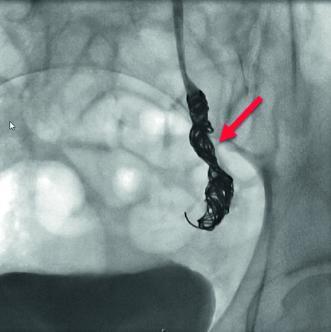

Typ Innere Beckenvene: Bei diesem Typ des Beckenvenenstauungssyndroms gründet die Symptomatik auf einer venösen Stauung der inneren Beckenvene. Der Rückstau des Blutes führt zu Krampfadern im kleinen Becken, welche die typischen Beschwerden eines PCS auslösen. Bei Patientinnen mit diesem Typ wird gelegentlich eine linksbetonte Beinvarikose assoziiert, während das rechte Bein keine Krampfadern aufweist. Häufige Ursache für diesen Typ sind Verengungen der Vena iliaca communis einschliesslich des May-Thurner Syndroms (Abb. 2) oder der Vena cava inferior.

Frauen im Alter zwischen 18 und 50 Jahren nach einer oder mehreren Geburten zählen zu der Risikogruppe. Obstruierende vaskuläre Anomalien wie das Nutcracker Syndrom (Kompression der linken Nierenvene durch die obere Darmarterie und Bauchaorta) oder das May-Thurner Syndrom (Kompression der linken Vena iliaca commuis durch die rechte Arteria iliaca communis) können zudem das Beckenvenenstauungssyndrom begünstigen.

In unserer Anamnese der seit vielen Jahren bestehenden Unterbauchschmerzen zeigten sich lageabhängige Beschwerden, die im Tagesverlauf zunahmen und in die Leistengegend sowie den Oberschenkel ausstrahlten. Ergänzt wurde die Anamnese durch Feststellung einer Pollakisurie und Dyspareunie. In der angiologischen Diagnostik konnte mittels farbkodierter Duplexsonographie eine Nutcracker-Anatomie (Einklemmung der linken Nierenvene zwischen der oberen Darmarterie und der Bauchaorta) und eine May-Thurner-Anatomie (Kompression der linken Vena iliaca commuis durch die rechte Arteria iliaca communis) festgestellt werden (Abb. 4, 5). In der MR-Phlebographie fanden wir ausgeprägte parauterine Varizen und eine stark erweiterte insuffiziente Vena ovarica links (Abb. 6).